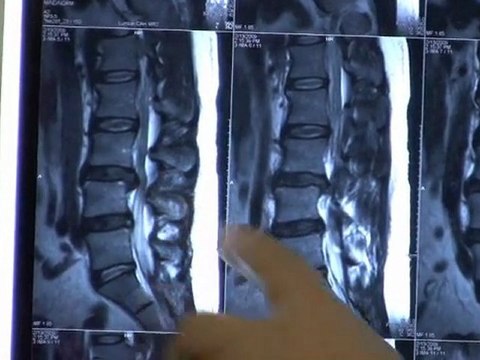

561-488-0225 Whether you’re looking for relief from severe chronic pain, or the pains of day-to-day living, Dr. Michael Marks and his staff can help. We provide gentle chiropractic care, specializing in several therapeutic modalities, including E-M-S ultrasound, spinal manipulation, cold laser therapy and massage by a licensed massage therapist. Utilizing state-of-the-art technology, we also provide spinal decompression through a DRX 9000c for both the cervical and lumbar region. We also have a digital x-ray machine on site to better diagnose our patients. We provide chiropractic services for all ages, from pediatrics to geriatrics, and also treat professional athletes. Whether you are a first-time or long-time chiropractic patient, our dedicated staff will provide you with honest, compassionate and full-service chiropractic advice and health care. If we feel you are not a chiropractic patient, we will refer you to a specialist that can help. Our office is open five days a week, and we also provide late night appointments. We accept almost all ppo’s and hmo’s. We’re located at 9325 Glades Road, Suite 108, in the Glades Medical Center behind Macy’s Furniture Gallery. Call us today to start your road to better health, 561-488-0225 .